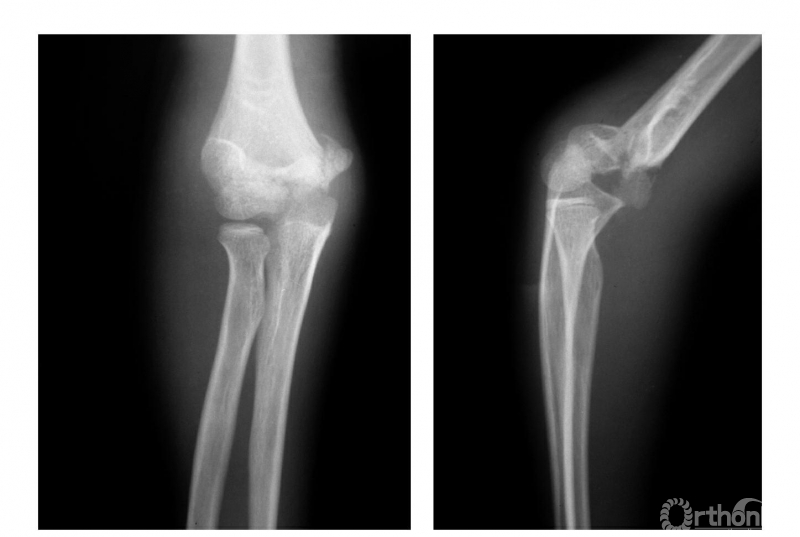

例1:肱骨髁间碎折,骨折远端后移并外髁与滑车关节面间少有分离(Ⅱ型)(图1)。

图1